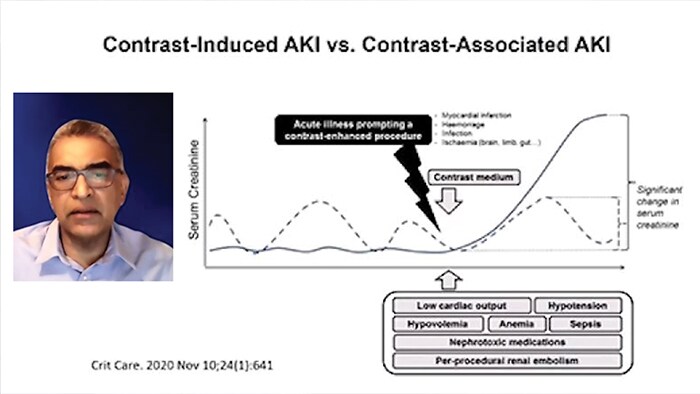

As low as reasonably achievable (ALARA) is a widely accepted approach to contrast use in PCI due to contrast induced acute kidney injury (CI-AKI).

Contrast medium has a "two-hit" model of direct contrast-induced renal tubular epithelial cell toxicity and vasoconstriction within the renal arteries that can last up to several hours, which results in the kidneys becoming ischemic and a decreased glomerular filtration rate (GFR), this in-turn causes a rise in creatinine. This complication adds to the patient’s length of stay and cost accrual to the hospital.

CI-AKI (also referred to as contrast induced nephropathy, CIN) is one of the major causes of hospital-acquired AKI: